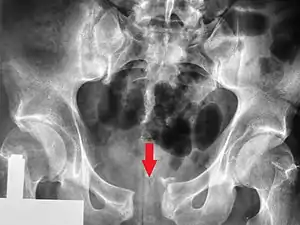

Open book fracture

One specific kind of pelvic fracture is known as an 'open book' fracture. This is often the result from a heavy impact to the groin (pubis), a common motorcycling accident injury. In this kind of injury, the left and right halves of the pelvis are separated at front and rear, the front opening more than the rear, i.e. like an open book that falls to the ground and splits in the middle. Depending on the severity, this may require surgical reconstruction before rehabilitation.[10] Forces from an anterior or posterior direction, like head-on car accidents, usually cause external rotation of the hemipelvis, an “open-book” injury. Open fractures have increased risk of infection and hemorrhaging from vessel injury, leading to higher mortality.[11]